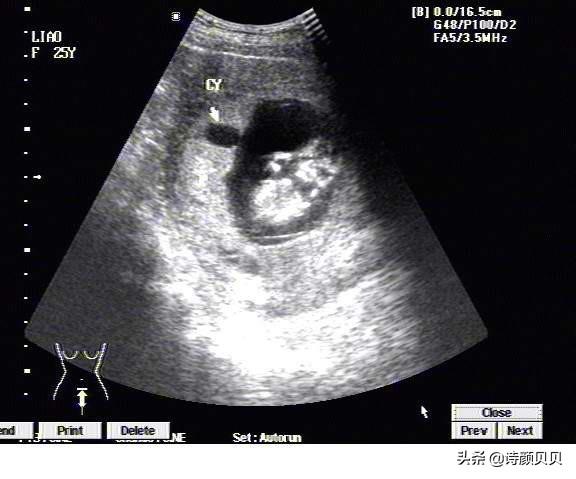

胚胎孕育过程中,受精卵常于30~40天形成胎囊,40~50天形成胎芽,50~60天形成胎心。但是在临床中常通过B超检查来观察胎心及胎芽,观察的时间为6~8周。

总的来说,40~50天形成胎芽,50~60天形成胎心,在6~8周左右可在B超下观察到。